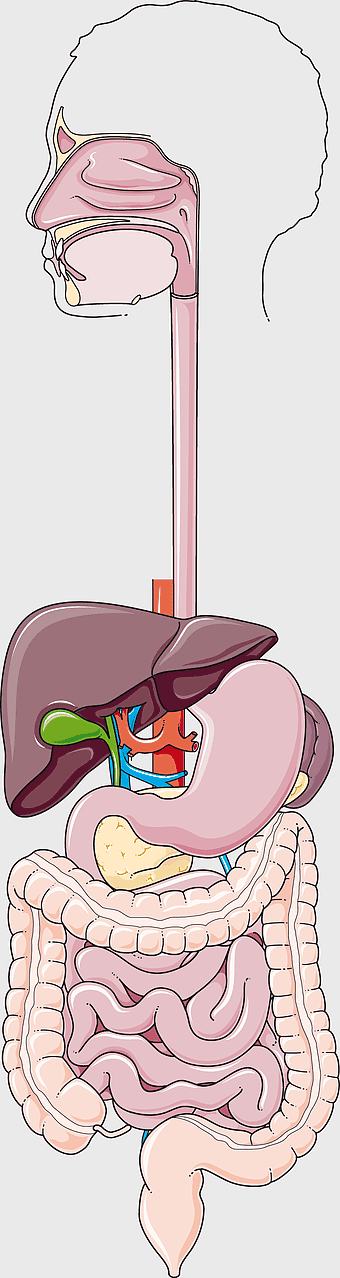

human gastrointestinal tract anatomy, human digestive system illustration, gastrointestinal disease symptoms, human body organ diagram, internal organ visualization, medical anatomy study, digestive health awareness -

human digestive system, gastrointestinal tract anatomy, liver function, stomach and intestines, digestive health, internal organs diagram, human body systems -